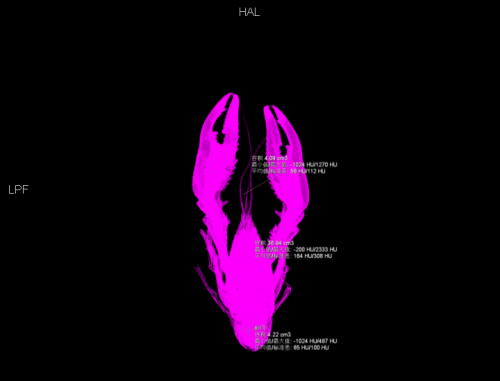

两部分可食用组织体积合计为 8.3ml,总体积占比为 22.47%。根据CT值推断,虾肉的密度比整虾密度低,因此,按重量计算的可食用部分占比会更低一些。按这个比例推算,本次受试小龙虾中至多1/5为可食用部分。

两部分可食用组织体积合计为 8.3ml,总体积占比为 22.47%(作者供图)

可食用部分 CT 三维重建,上方为螯足,下方为腹部虾肉(作者供图)

考虑到螯足内的肉很难被吃干净,而且很多小体型的虾或者某些时期的小龙虾螯足内几乎没有肉,因此可食用部分占比会更低一些。

按上述比例估计,一斤小龙虾,最后吃到嘴里的大约只有 50~100g。